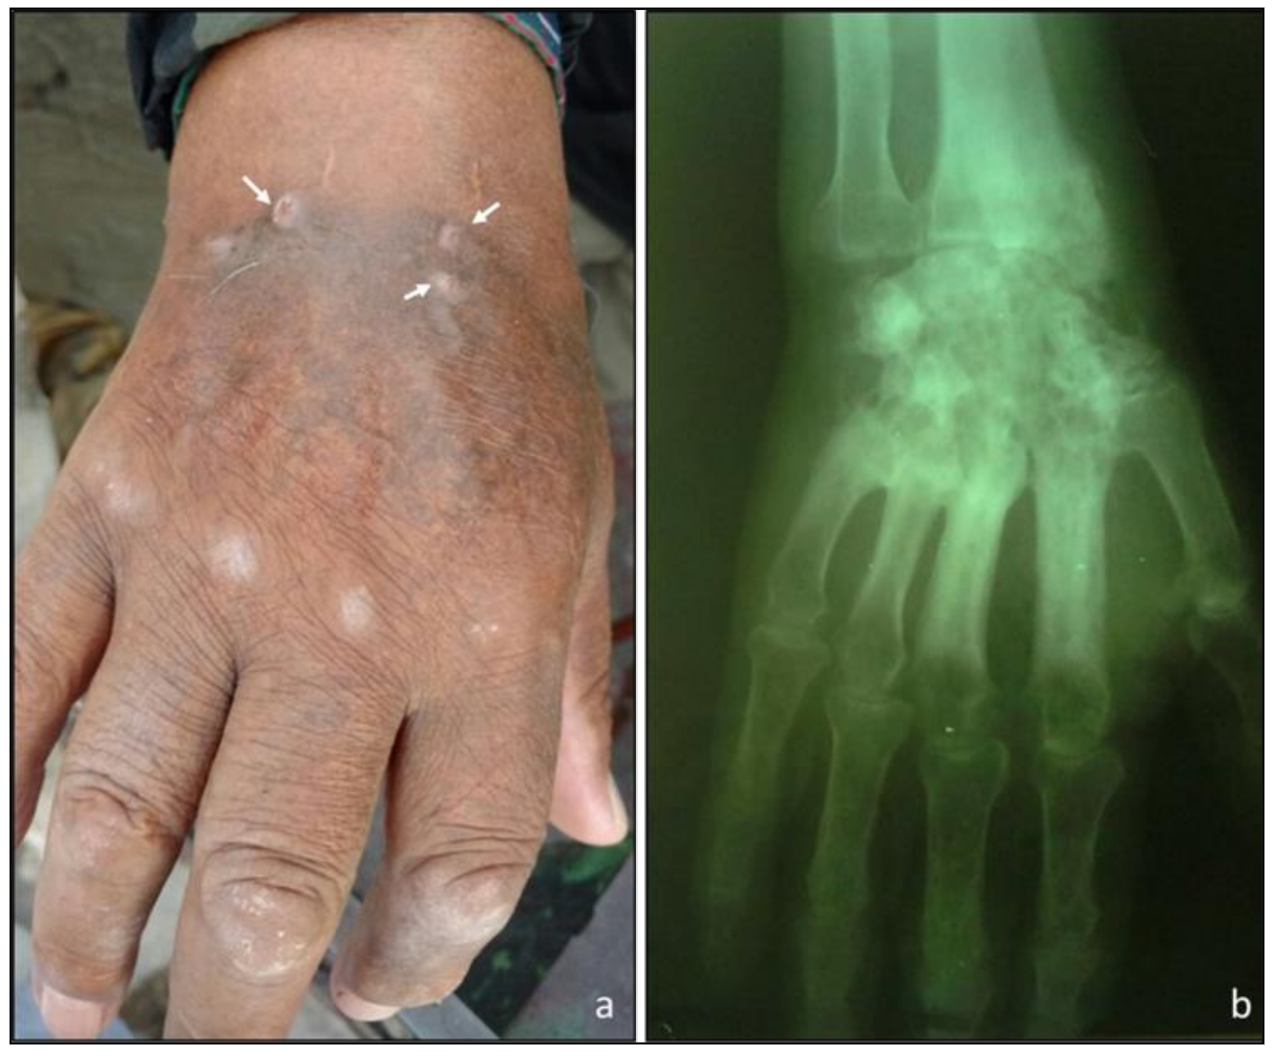

| Scedosporium americanum sp. nov. | DMic 165285 | Subcutaneous mycosis (hand), 2016 | MT813171 | MT803032 |